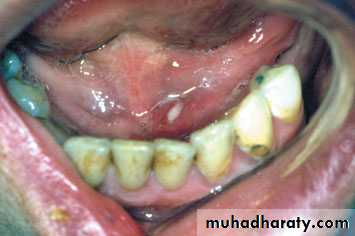

Acute suppurative submandibular sialadenitis. There ispus extruding from the left sublingual papilla.